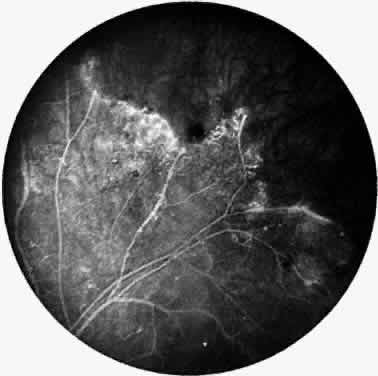

Signs of ocular inflammation are commonly encountered in Eales' disease, especially early in its course. Vascular sheathing is seen in most patients (Fig. 1). The degree of sheathing ranges from thin white lines on both sides of the blood column to thick heavy exudative sheathing. Areas of sheathing frequently leak dye with fluorescein angiography (Fig. 2). However, there is not a direct correlation between the regions of sheathing and staining.

Fig. 1. Vascular sheathing. A. Thin white lines surround retinal venule. B. Exudative-type arteriolar sheathing.

Fig. 2. Fluorescein angiogram demonstrating abnormal vascular staining in a patient with Eales' disease. There was venous sheathing in these areas.

In the century since Henry Eales' observation of altered retinal veins, many investigators have described Eales' disease as a primary disease of altered retinal veins. Elliot and Harris suggest the term periphlebitis retinae for this disorder.4 However, recent reports suggest equal involvement of arteriolar and venular sheathing. Because of the evidence of arteriolar involvement (see Fig. 1B), this disease should be considered as a retinal vasculitis or vasculopathy. Others have used the term primary retinal perivasculitis.8 Cystoid macular edema, vitreal cells, keratic precipitates, and cell and flare in the anterior chamber have been observed in patients with Eales' disease.3